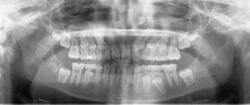

A panoramic radiograph of a 9 year old in mixed dentition